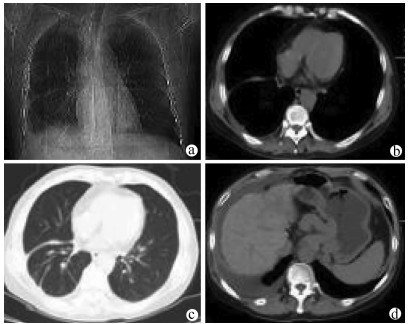

胸膜腔内注射聚桂醇治疗难治性肝性胸水1例报告

李常洲, 李建辉, 郝欣, 姜海斌, 王爱民, 花海洋, 齐静, 张静哲

2021, 37(9): 2177-2179. DOI: 10.3969/j.issn.1001-5256.2021.09.033

摘要(823) HTML (236) PDF (2488KB)(51)

摘要: